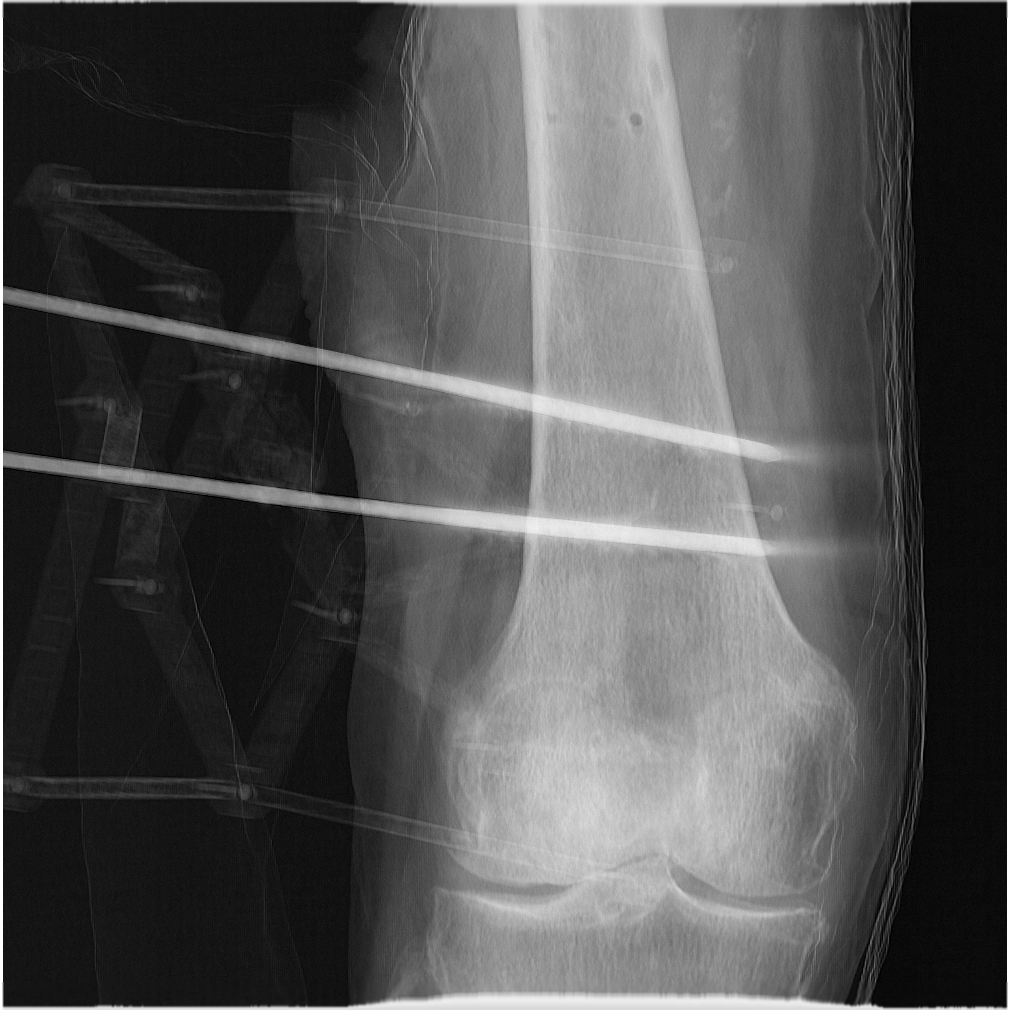

Based on this definition, we propose dividing the femur into three convex substructures, each associated with a contour category, that are convex with respect to an observer (the C-arm) rotating around the diaphysis’s main axis: diaphysis, the medial condyle and the lateral condyle (shown Figure 1) of class indices in the following.

Registration An evaluation of multiple registration strategies was performed. The commercial intensity-based method ImFusion [6], which is considered a leading approach in multi-view intensity-based registration. This method requires manual initialization to function effectively. Corresponding landmarks are manually placed by clicking correspondences in the images and CT data to achieve a rough alignment of the bone. Specifically, four corresponding points are manually marked in the images and CT using the provided GUI. These correspondences are then used to initialize the registration, bringing it close to the final solution. All registration parameters were kept at their default settings during this process. Additionally, we included a related ICP and contour-based approach from Zhang et al. [9], with improvements by replacing Canny edge detection [21] with a deep-learning-based edge detection method [22] in our implementation of the method. This method utilizes the bone silhouette, without any semantic substructures, during optimization. We did not find more open-source implementations of multi-view registration methods. Table 4 summarizes the registration errors on our real-world dataset. For each registration, we used two views with a perspective change of at least 45 degrees. Since our method does not require initialization, we set fixed values for all experiments, i.e., translations of +30mm, -40mm, +5mm and Euler angles of -17.18°, 0°, 17.18°. There are a total of 30 runs (6 runs per subject 5 subjects) presented for each method. As described in Section 4.2, we use the mRPD as evaluation metric. The evaluation setup consisted of 3 control views, seperated by 9° each situated in between the two X-ray images used for registration. Our method achieved an mRPD of 0.67mm, compared to 5.35mm for the commercial method and 4.03mm for Zhang’s method. In some cases, our method produced incorrect registrations. We demonstrate empirically in Online Resource 1 that these failing registrations can be automatically detected using the reprojection errors during the ICP optimization, allowing the registration to be restarted. Note that this property holds under certain conditions regarding the quality of the contour segmentation results.

Impact of Occluding Contours A key innovation of our method is the use of component-level contours, as described in Section 3. Their benefit in the ICP optimization is significant when compared to the object-level contours in Zhang’s method, as shown in Figure 4 and Figure 5. Zhang’s method, which does not incorporate substructures, is more prone to getting trapped in local minima, as shown by the larger errors compared to our method.

Visual Results Figure 6 shows a qualitative comparison of our method with ImFusion. Green contours represent the ground truth, and the colored dots show reprojected points from the registered decimated bone mesh.